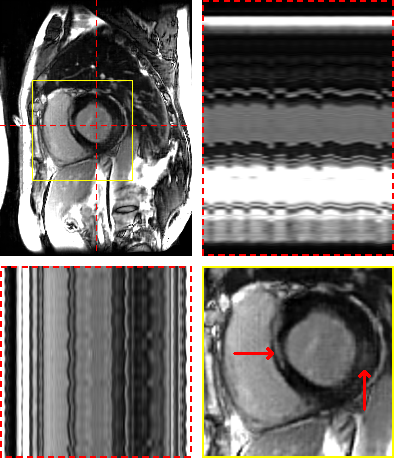

Figure 3: Exemplary MRXCAT phantom reconstructions. Each sub-figure illustrates an end-diastolic frame, temporal profiles, and a close-up on the heart. Red arrows show an area with an artifact in LR-DIP that is suppressed in M-DIP.

3.2 In-vivo study

Figure 4 and Figure 5 illustrate the results for an exemplary real-time cine dataset and a free-breathing single-shot LGE dataset, respectively. Scoring results are given in Table 3 and Figure 6. M-DIP achieved highest scores in all considered criteria. Sharpness of real-time cines was scored significantly higher in M-DIP than in any other method. M-DIP and CineVN were scored equally in terms of noise/artifacts in the real-time cines, where only L+S received significantly lower scores than the other methods. In free-breathing single-shot LGE, M-DIP was scored significantly higher than both LR-DIP and L+S. Cine reconstruction took approximately 30 min with M-DIP and 45 min with LR-DIP, while LGE reconstruction took approximately 15 min with M-DIP and 10 min with LR-DIP.

In the first study, we simulated multi-coil undersampled k-space data using free-breathing real-time cardiac cine MRXCAT phantoms. M-DIP outperforms both L+S and the recently proposed LR-DIP method in terms of PSNR, NRMSE, and SSIM. The performance gap between M-DIP and L+S is substantial, as L+S produces images with high levels of noise. While the performance advantage of M-DIP over LR-DIP is more moderate, visual inspection reveals that LR-DIP consistently introduces motion blurring around the myocardium. In contrast, M-DIP captures cardiac motion more accurately, as shown in Figure 3.